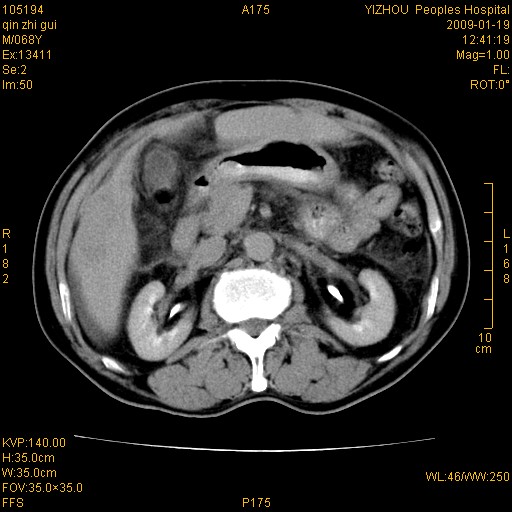

以下是引用随光逐影在2009-1-21 16:11:00的发言:[br]1)考虑肝右叶肝癌并肝静脉及门静脉瘤栓形成。2)肝硬化,少量腹水。3)胆囊炎。4)右侧少量胸腔积液。

病灶外缘凹凸不平,平扫低密度,增强动脉期有强化,门脉早显,静脉期及延期呈延迟强化,结合病史考虑右肝前叶巨块型肝癌可能性大,强化表现不除外胆管细胞癌